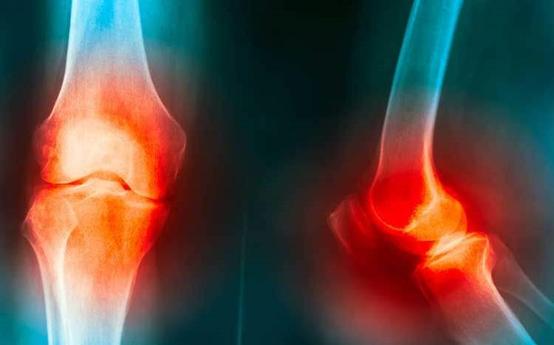

除了就医吃药,良好的自我管理行为对于疾病症状控制、关节功能保护等具有积极影响。美国风湿病协会强烈推荐骨性关节炎患者进行自我管理。

在医护人员的协助下,患者本人承担一些预防性或治疗性的卫生保健行为,以促进或维持健康即自我管理行为。骨性关节炎患者的自我管理行为包括运动锻炼、情绪管理、与医生的沟通、饮食调整等。

1、运动锻炼,包括体能锻炼和耐力锻炼。这两种锻炼不是单纯的增强体质,也是疾病治疗的一部分。体能锻炼通过肌肉的等长或等张收缩来加强关节周围肌肉及韧带的力量,从而加强关节稳定性,起到关节保护的作用。如改善膝关节的功能,通过股四头肌的肌力训练,增强股四头肌肌力及周围韧带力量,能有效减轻膝关节疼痛。